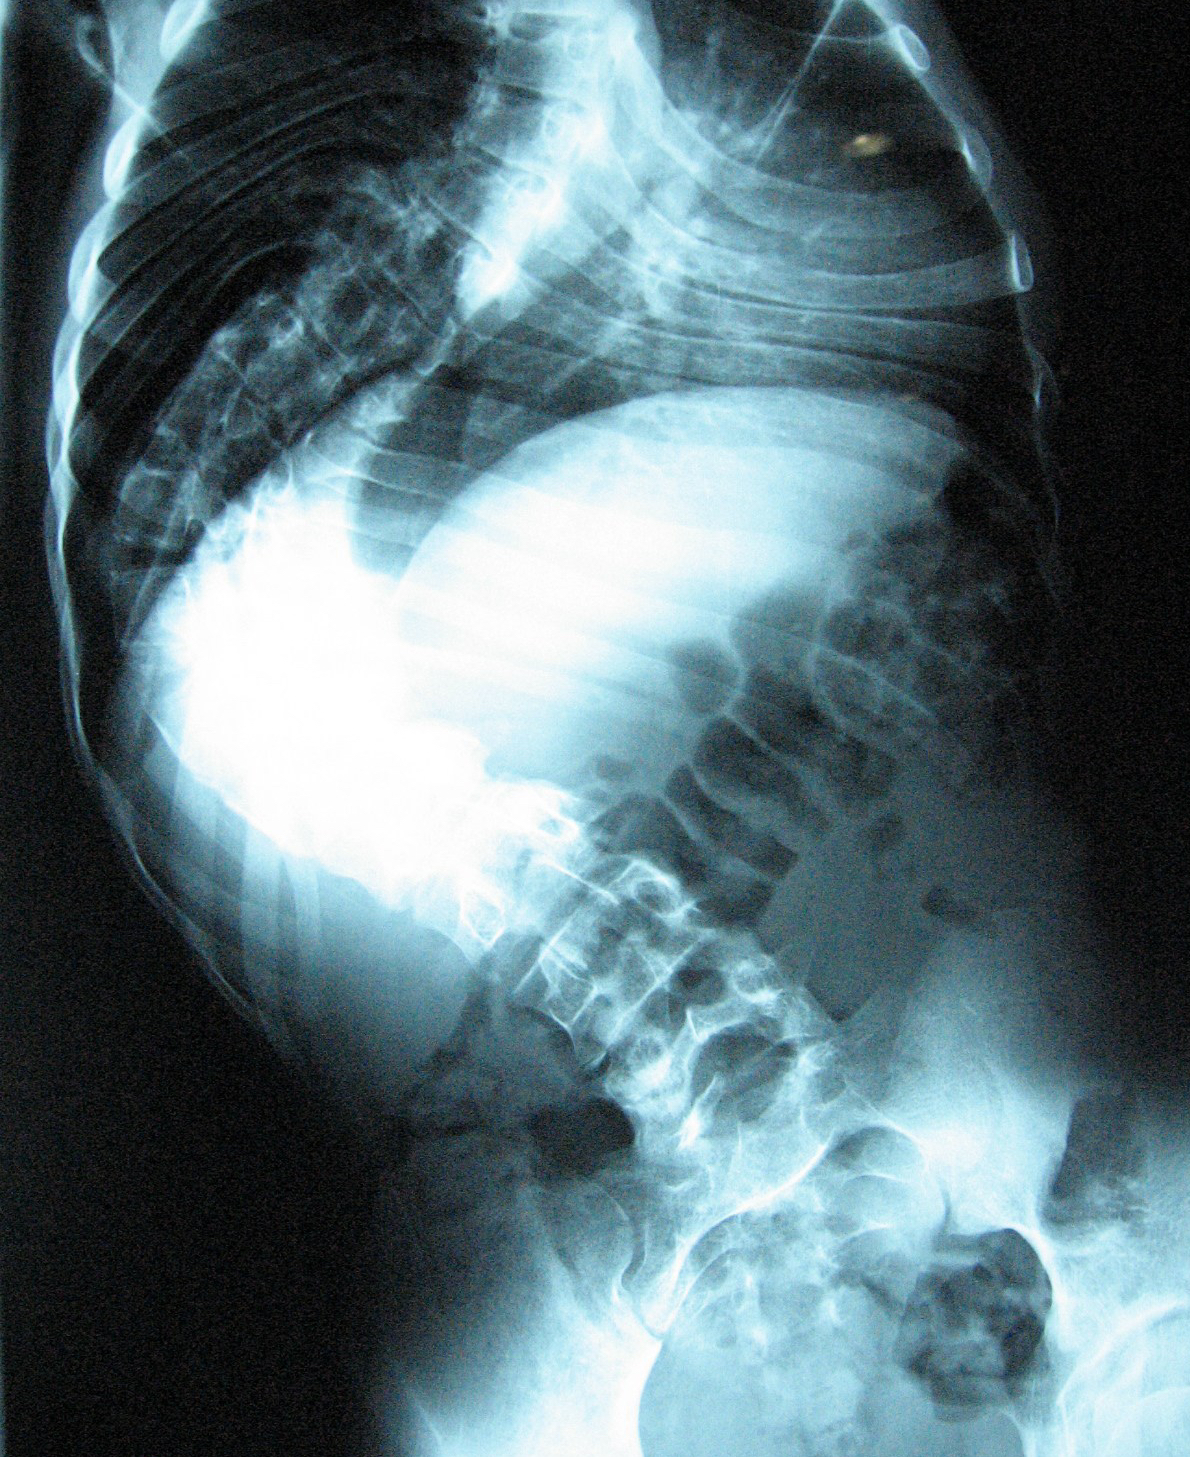

Scoliosis is an abnormal sideways curve in the spine. Normally the spine has a straight alignment when seen from the front or back. A sideways curve in the spine can develop due to a various reasons at different stages of growth. As the spine grows taller, there is a tendency for the curves to worsen and can become severe by the time the kid reaches skeletal maturity.

The curve in the spine is associated with rotation of the spinal column to one side. As the ribs attached to the spine rotate along with it, it leads to a rib hump in the back on one side and prominence of chest wall in the front on the other side. A curve in the lower spine leads to asymmetry in the waist lines. It is usually the rib hump or asymmetrical waist line that brings the problem to notice, usually at a time when the kid is growing rapidly.